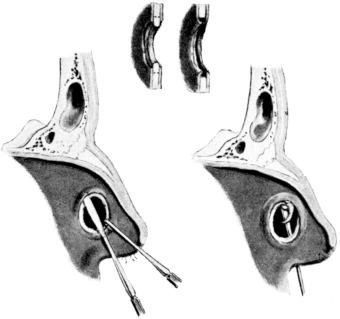

| 190. | Lines of Incisions in Intratympanic Operations | 341 |

| 191. | Cutting through Intratympanic Adhesions | 344 |